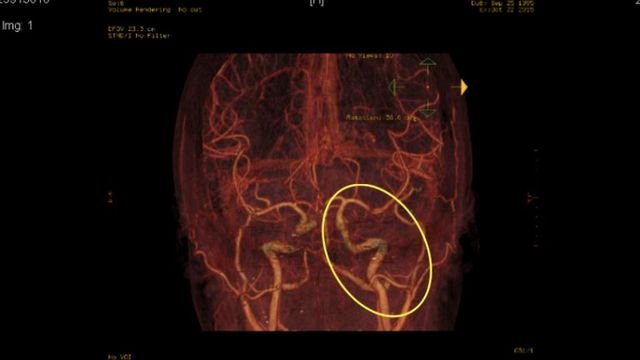

La terrible historia de Sergio en el SES: «Tenía otra prótesis colocada en el cerebro sin consentimiento y sin justificación ninguna, porque esa arteria estaba completamente sana»

Una presunta negligencia médica perpetrada por un radiólogo intervencionista del Hospital Universitario de Badajoz (Servicio Extremeño de Salud) deja a un joven paciente con mareos […]